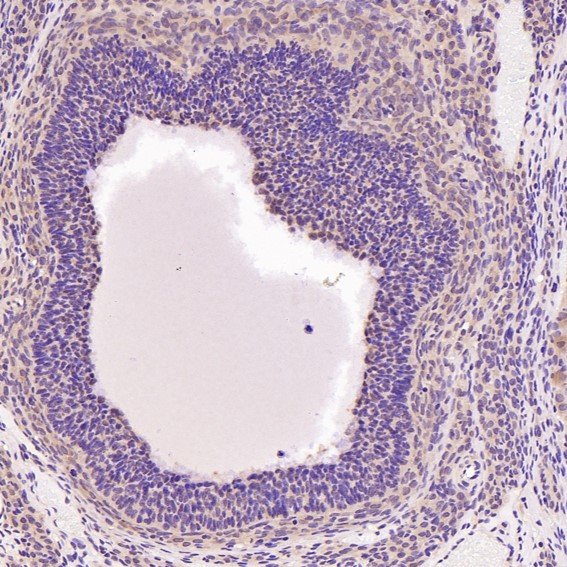

Immunohistochemical analysis of paraffin-embedded Rat ovary, using the Antibody at 1:200 dilution.